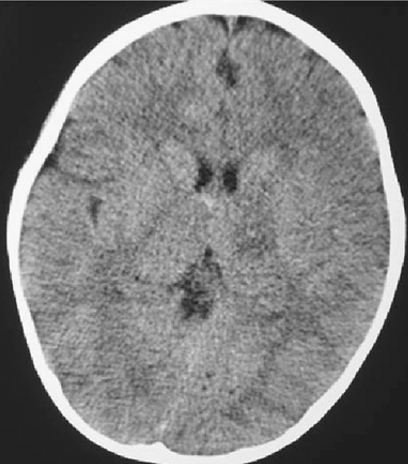

\_\_\_\_\_\_\_\_\_ is the most common CT abnormality in TBI patients (moderate-severe)

subarachnoid hemorrhage

Signs of intracranial HTN on CT (3)

1. compressed lateral ventricles 2. attenuation of the sulci & gyri 3. poor white/gray matter distinction